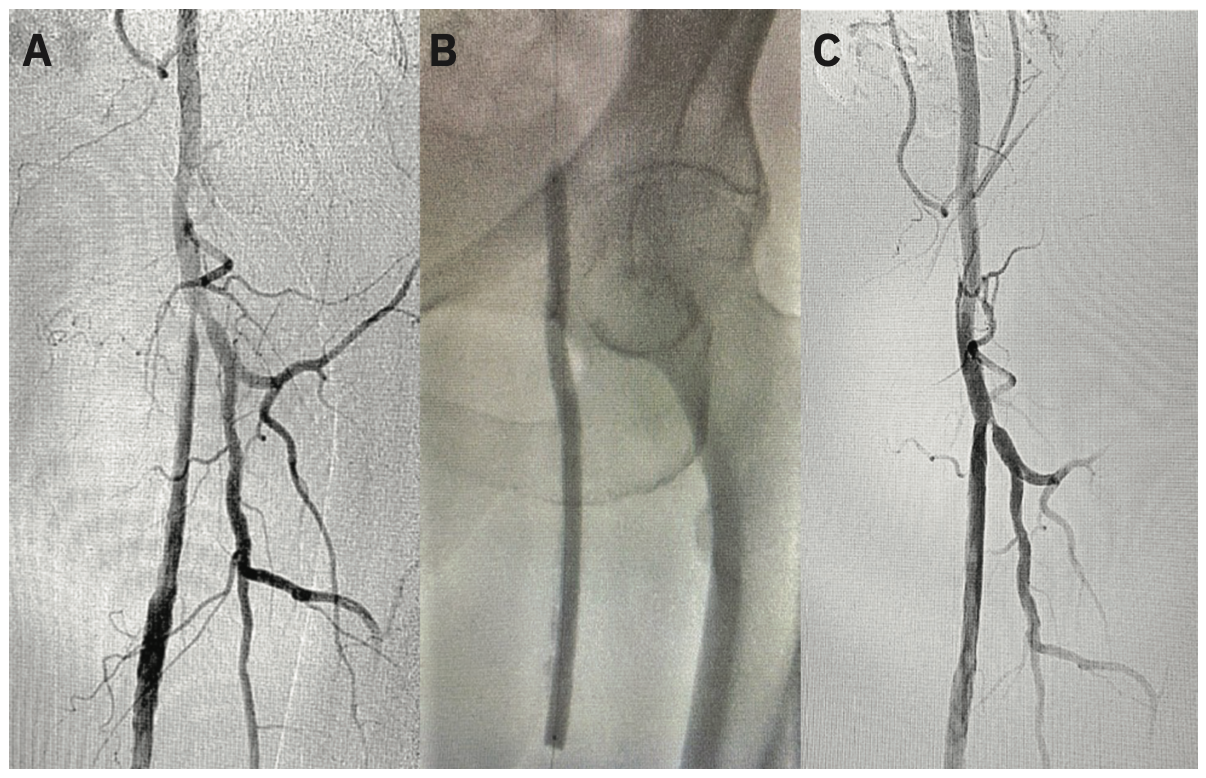

Access was obtained in the right radial artery with ultrasound guidance, and a 6 French (Fr) Glidesheath Slender (Terumo Interventional Systems) was placed. A standard radial cocktail was administered. Over an .035-inch J-wire, a 4 Fr 150 cm Glidecath Multicurve (Terumo Interventional Systems) with side holes was advanced into the distal abdominal aorta. Iliac angiography was performed. A 400 cm angled .035-inch Glidewire (Terumo Interventional Systems) was then used over the Glidecath to selectively cannulate the right popliteal and external iliac arteries for infrapopliteal and femoral arterial angiography, respectively, followed by the left popliteal and external iliac arteries. Digital subtraction images demonstrated severe proximal to mid SFA disease in the right leg with 3-vessel runoff (Figure 1A), and severe disease of the left leg up to the mid SFA, with 3-vessel runoff. (Figure 2A). Pressure gradients were measured on pullback from the popliteal artery to the common femoral arteries, confirming hemodynamic significance of the lesions. At this time, we proceeded with transradial endovascular intervention of the bilateral femoropopliteal arteries.

The Glidecath was removed. Heparin was administered to therapeutic activated clotting time (ACT). Over the .035-inch Glidewire, the Glidesheath Slender was removed and replaced with a 6 Fr 119 cm R2P Destination Slender Guiding Sheath (Terumo Interventional Systems), which was advanced to the level of the left common external iliac artery. An .018-inch 335 cm ViperWire (CSI) was taken to the infrapopliteal arteries. The entire left SFA into the moderately diseased proximal left popliteal artery was ballooned with a 5 mm x 200 mm Metacross balloon (Terumo Interventional Systems), followed by drug-coated balloon (DCB) angioplasty in the proximal to mid SFA with a 6 mm x 150 mm IN.PACT 018 DCB (Medtronic) (Figure 2B). The IN.PACT 018 DCB has only recently become available in the U.S. in a 200 cm shaft length on an .018-inch platform, facilitating femoropopliteal treatment from the transradial approach. Following left leg intervention, the .018-inch wire was removed, and the sheath was pulled back over the .035-inch Glidewire, and then advanced over the dilator into the right external iliac artery. The proximal to mid right SFA was similarly treated with a 5 mm x 200 mm Metacross balloon, followed by DCB with a 6 mm x 150 mm IN.PACT 018 (Figure 1B). Final angiograms of both legs showed no significant residual stenosis or flow-limiting dissections (Figures 1C and 2C), with 2+ distal pulses.